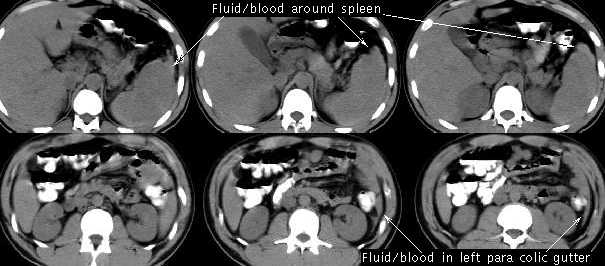

A twenty-six year old female presents to your Emergency Room after a motor vehicle accident. The patient reports that she was a pedestrian on South University Avenue and while crossing the street was struck by a car. The patient's only complaints are abdominal tenderness and left shoulder pain. On physical exam you note that her vital signs are: blood pressure (BP) 90/60, heart rate (HR) 110, and respiratory rate (RR) 12. Her abdomen is tender on palpation of the left upper quadrant, with a faint tire mark over that area; in addition you detect crepitus (indicating fractured ribs) over the 9th,10th, and 11th ribs on the left side. You order a CBC which demonstrates an increased white blood count and a decreased hematocrit. You perform a diagnostic peritoneal lavage (DPL) and order a CT . The DPL has a bloody drainage (through which you cannot read a newspaper) and CT confirms a complete splenic rupture and fractured ribs. The patient is taken to the O.R. for a splenectomy , and a pneumococcal vaccine is delivered to the patient.

5. What are the signs and symptoms of acute splenic rupture?

Hypotension, left upper quadrant pain, peritoneal irritation, and referred pain to the left shoulder.